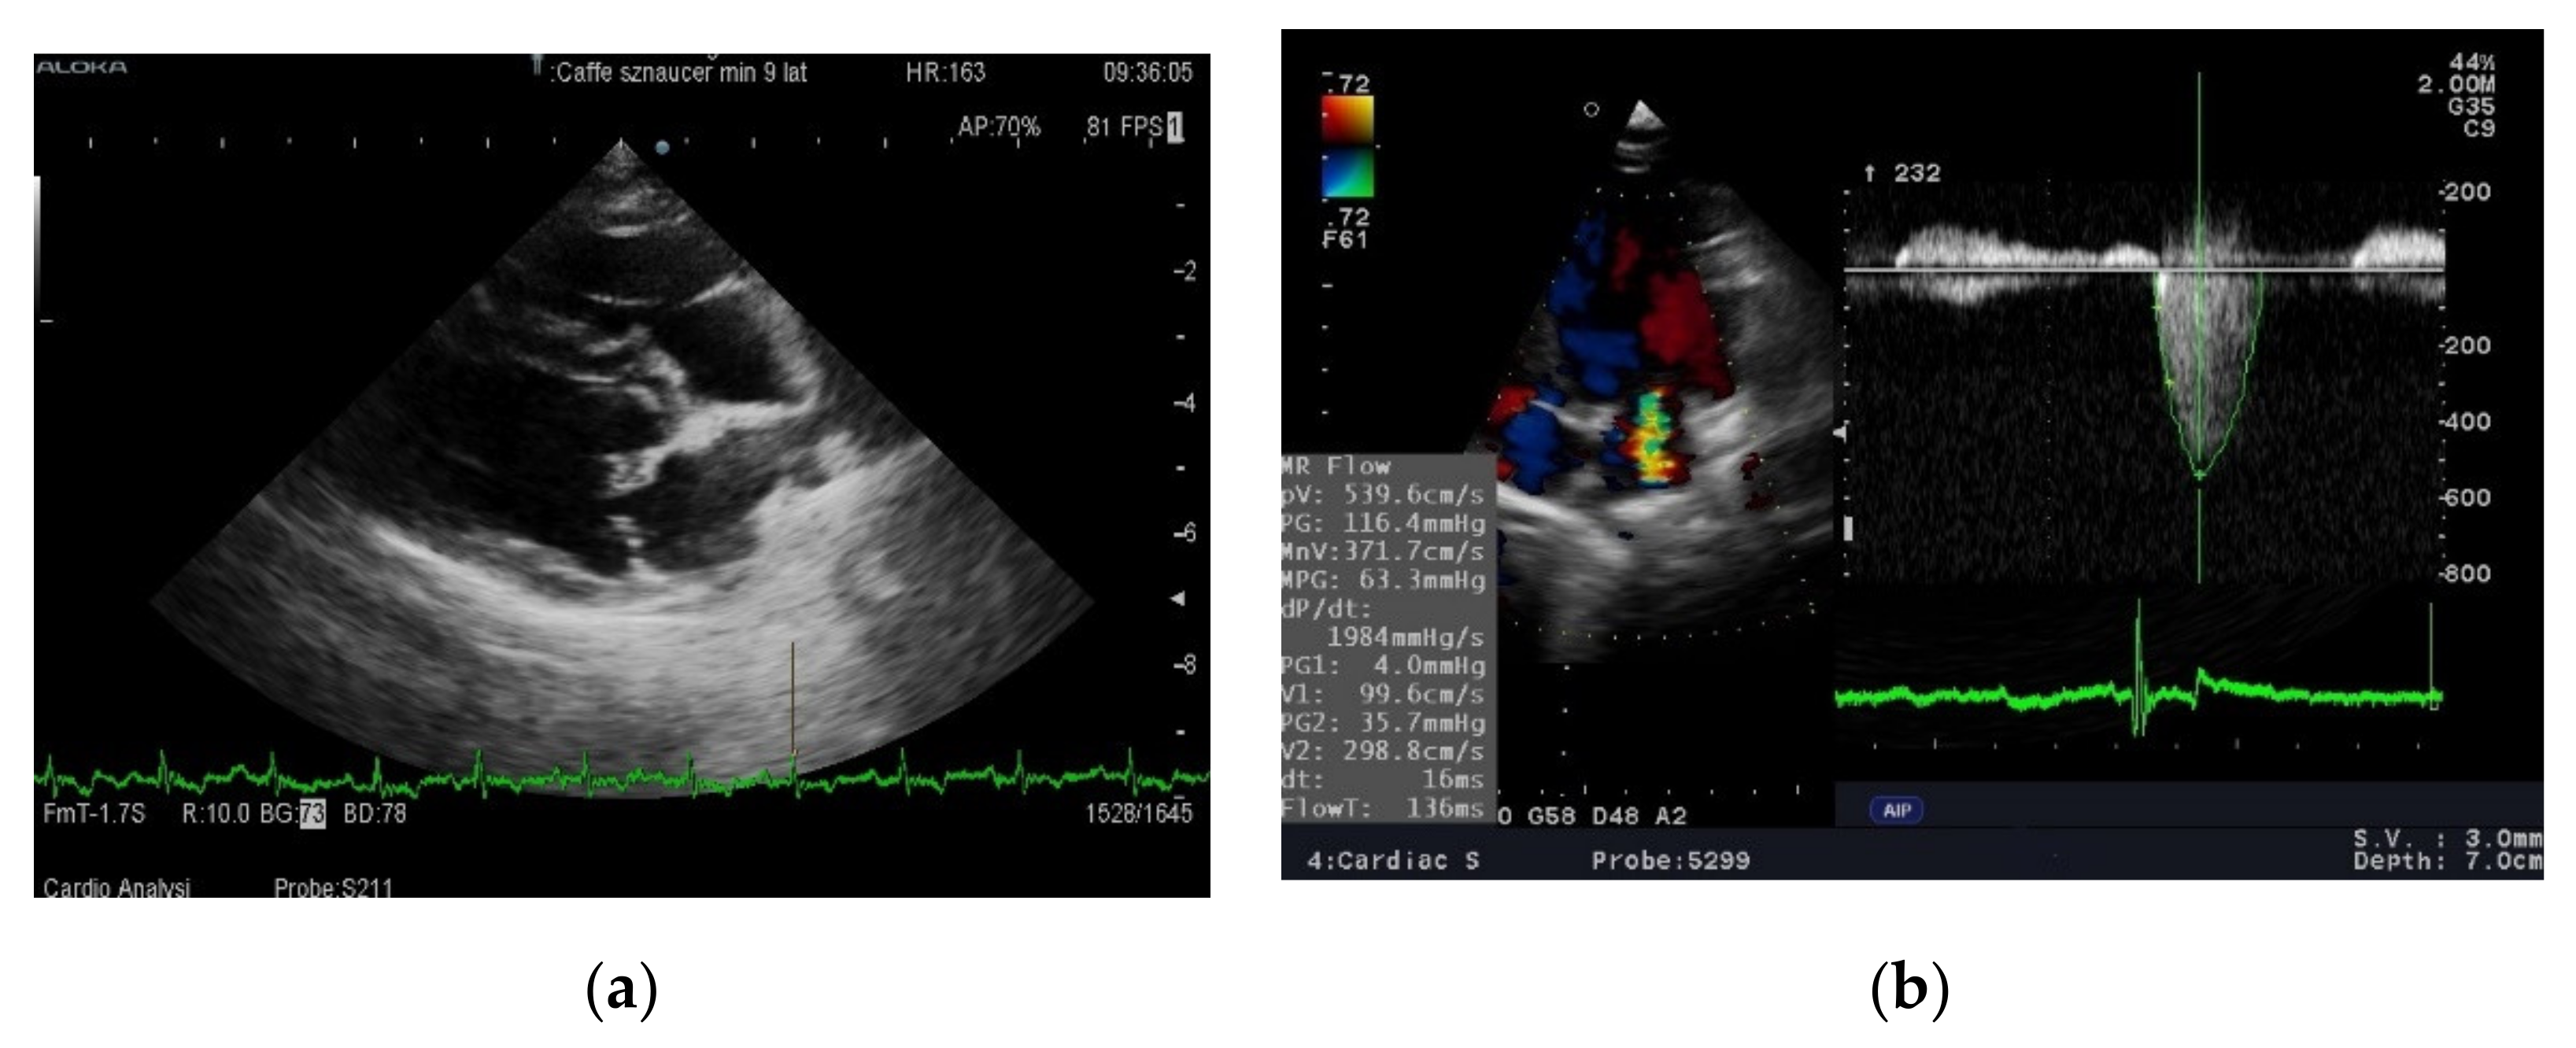

Standard ambulatory ECG examinations were performed using the digital BTL® electrocardiograph in the standing position. A standard ECHO examination was performed using the Aloka Alpha 6 (Osaka, Japan)® with a 5–7.5 MHz sector probe. The aortic diameter (Ao), left atrium diameter (LA), HR: heart rate; LA/Ao: left atrium to aorta diameter ratio; end-diastolic (RVIDd) internal diameter of the right ventricle, end-diastolic (LVIDd) and end-systolic (LVIDs) internal diameter of the left ventricle, thickness of the interventricular septum at end diastole (IVSd) and end systole (IVSs), and the end-diastolic (LVFWd) and end-systolic (LVFWs) thickness of the free wall of the left ventricle were measured. The shortening fraction (FS) of the left ventricle was calculated using the Teicholz formula (FS = [(LVIDd−LVIDs):LVIDd] × 100) [13]. Mitral regurgitation, maximal flow of mitral regurgitation (MR) was measured using continuous wave Doppler technique from the left parasternal two- or four-chamber view. All the dogs included in the study had degenerative malformations on the tips of the mitral leaflets and elevated left atrium/aorta ratios (stage B2 according to ACVIM classification) [11]. Dogs in stage C2 additionally had clinical signs of cardiac failure (exercise intolerance and occasionally cough). All these dogs have mitral regurgitation flow into the left atrium (visualized and measured using the Doppler technique) (Figure 1a,b). The experiment was double blinded: owners and cardiologist were blinded to diet received by dog.

Figure 1. Echocardiographic examination of a dog with MMVD (a) 4th right intercostal space, long axis four chamber view. Tips of the mitral leaflet are thickened and deformed by degenerative processes—arrow. (b) On the left side of image is presented a multi-colored, turbulent jet of blood flowing back into the left atrium during systole. 5th left intercostal space, apical four-chamber view. On the right side—measurement of mitral regurgitant flow using continous Doppler method.